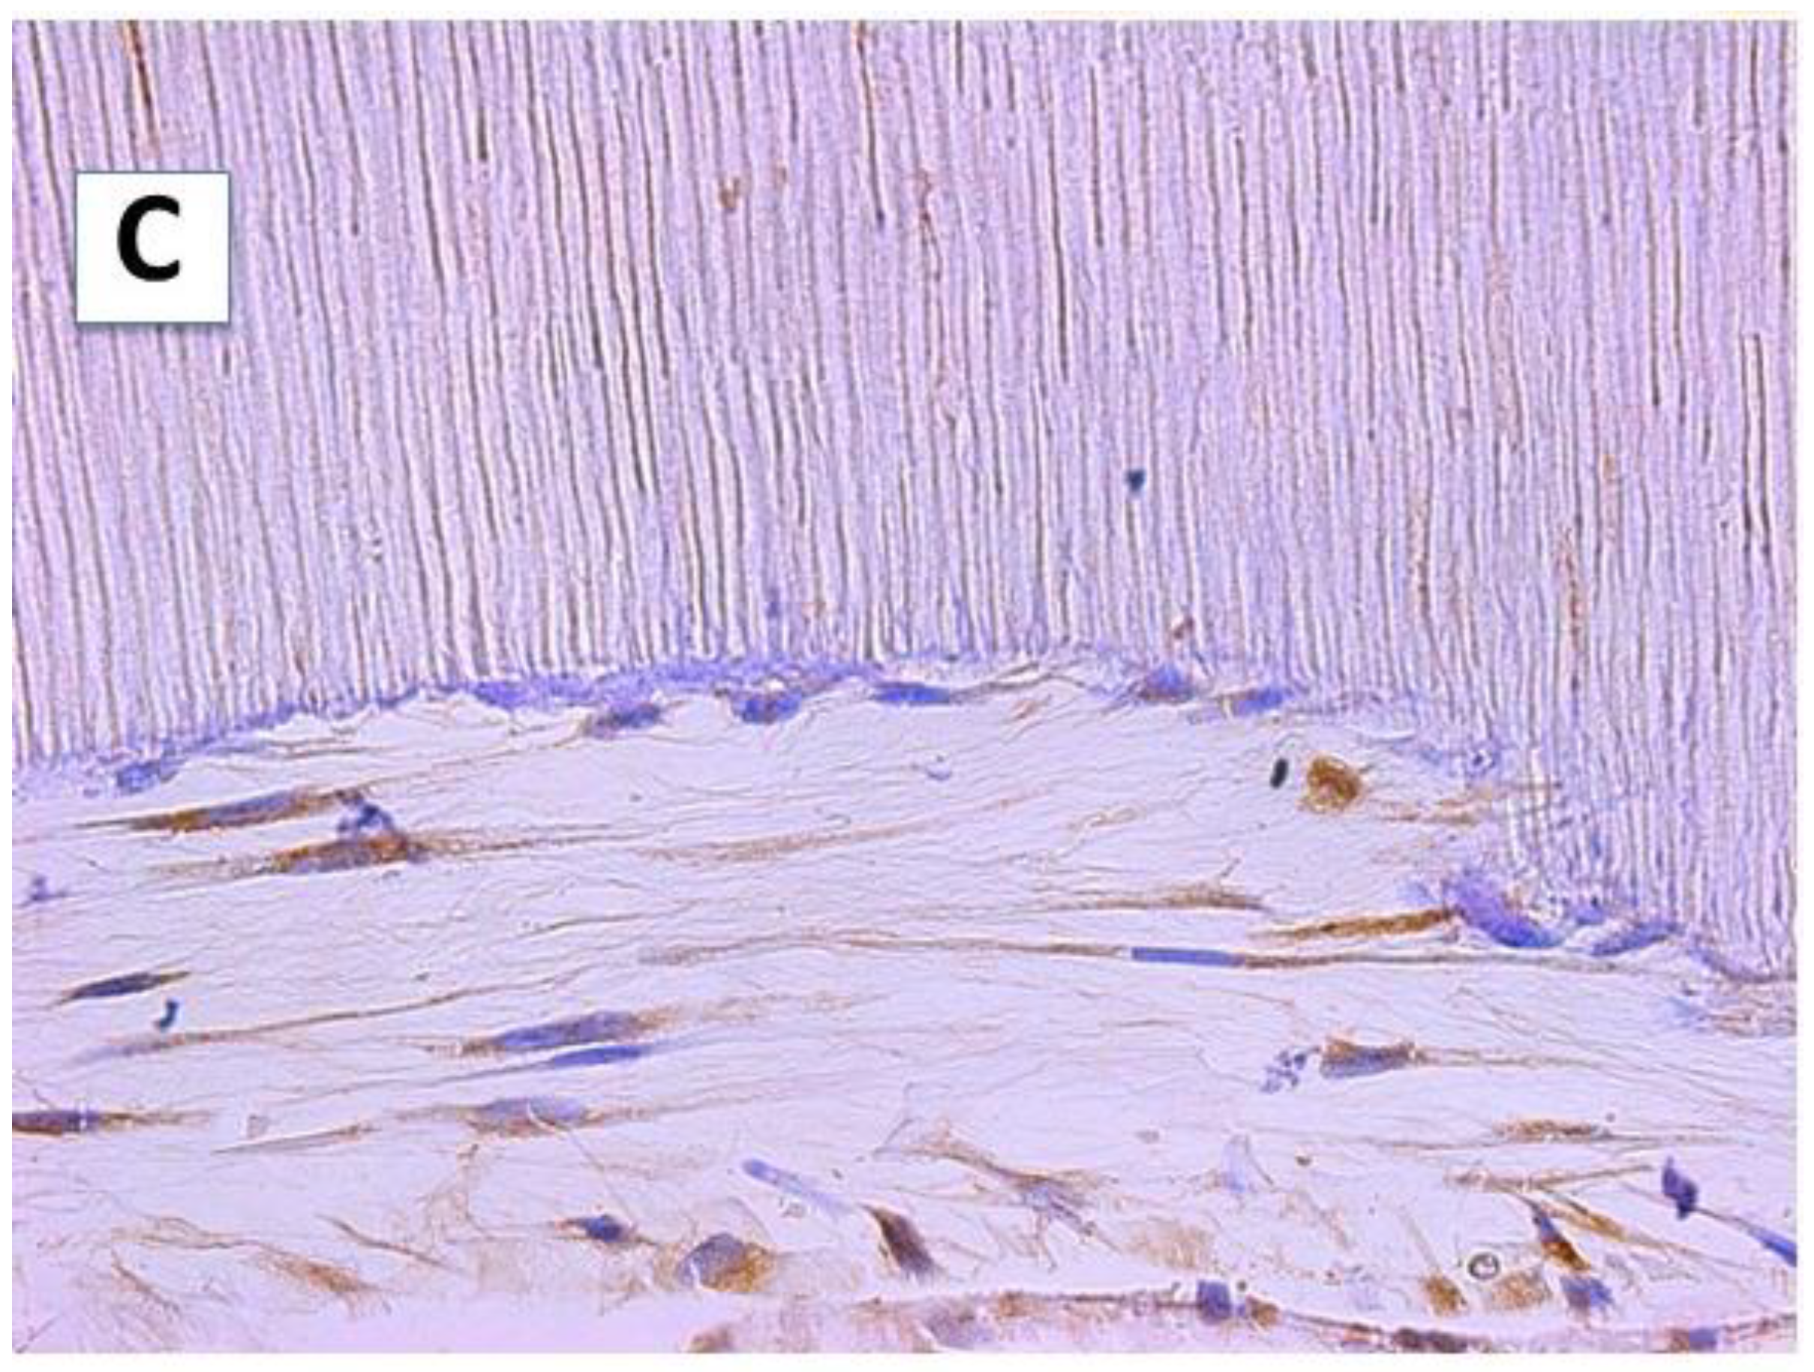

Characteristic reticular connective tissue was observed, with fine collage fibers and deposits of dentin sialophosphoprotein (DSPP) on the surfaces of the scaffolds with accessible dentinal tubules (Figure 1). The hDPSCs acquired an odontoblast-like morphology, which are characterized by a flat shape and growth that is perpendicular to the dentin scaffold surface. Several cellular processes were observed within the dentin tubules (Figure 1, panel B). The cells presented a stellate morphology, with little cohesion between them, developing cytoplasmic extensions as an odontoblastic process towards the dentinal tubules, and in some cases, several extensions were visible in the same cell. These odontoblast-like cells were positive for DSPP, which was also detected in the cell processes occupying the dentin tubules (Figure 1, panel C). However, DSPP deposits in the synthesized intercellular matrix were scarce and hardly visible.

Figure 1.

The hDPSCs were cultured on the surface A (SA) of the scaffold for 6 weeks and processed by light microscopy. (A) The hDPSCs adopted an odontoblastic morphology, emitting processes within the dentinal tubules; the cells were surrounded by a reticular-like intercellular matrix with fine collagen fibers. Masson’s trichrome staining (40×). (B) Close-up of the area delimited by the square in (A). On the dentin surface with the tubules perpendicular to the surface, the extracellular matrix was low in collagen and some hDPSCs emitted several processes (arrows) within the dentinal tubules (100×). (C) Immunohistochemical analysis of the hDPSCs cultured on the SA. The cells showed intracellular DSPP deposits, both in the cell body and in the cellular processes located within the dentinal tubules (40×).